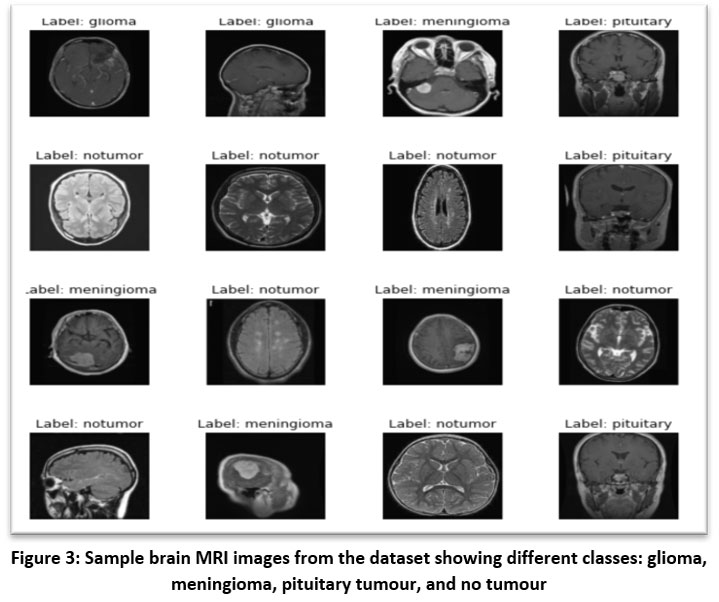

![]() |

Figure 3: Sample brain MRI images from the dataset showing different classes: glioma, meningioma, pituitary tumour, and no tumourClick here to view Figure |

Figure 3 above presents a grid of sample brain MRI images representing the four classes used in the classification task: glioma, meningioma, pituitary tumour, and no tumour. These images visually demonstrate the diversity in tumour appearance, anatomical location, and scan orientation. Each image is labeled according to its ground truth class, providing insights into the morphological characteristics that distinguish each category. For instance, glioma and meningioma can be seen with irregular masses in different brain regions, while pituitary tumours are located near the base of the brain. The “no tumour” images exhibit normal brain structures without any visible abnormalities. This visualization emphasizes the complexity of tumour detection and the necessity for automated feature extraction techniques, such as those employed in the EfficientNet-B0-based models, to accurately differentiate between subtle pathological features.